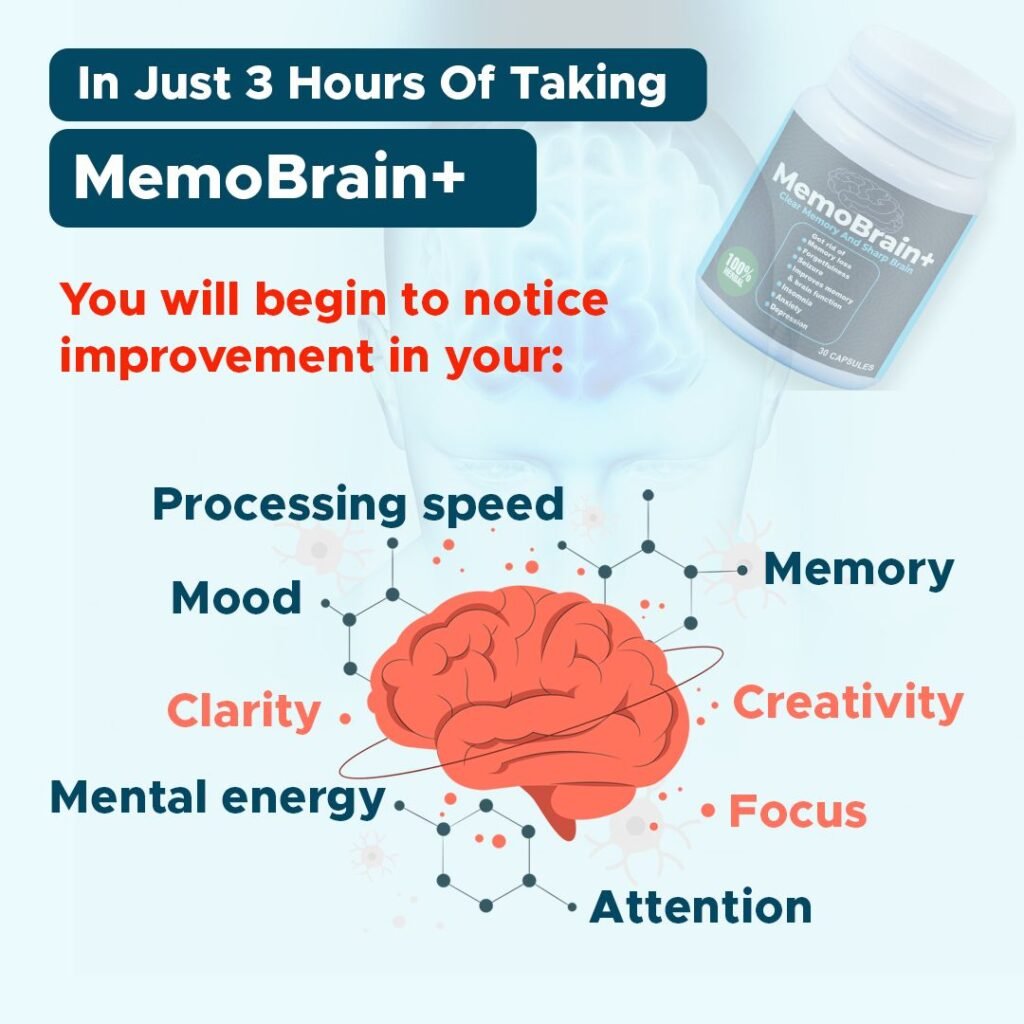

Powerful Sacred Memory & Brain Heal-All Herb Makes Your Memory Stronger, Boosts Brain Cells And Energy, Gets Rid Of Forgetfulness, Clears Seizure, Smashes Brain Fog And Increases Processing Speed… Starting In Just 3 Hours!

This sacred memory and brain heal-all herb will fix all your memory and brain problems starting in just 3 hours

MemoBrain+

MemoBrain+ is not formulated to only enhance your brain and memory…

MemoBrain+ is the best for you if you want to improve your brain and memory

MemoBrain+ will:

And you will begin to notice incredible improvement in your:

- Memory

- Motivation

- Focus

- Energy

- Clarity

- Attention

- Mood

- Processing

- Creativity

- Calmness